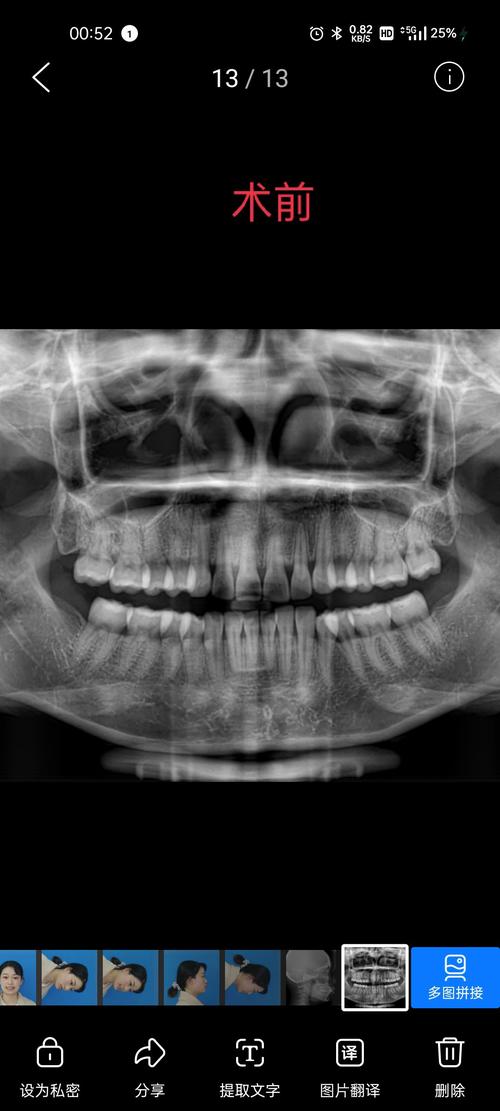

- 拍X光片(全景片、头颅侧位片)、取模、口内扫描(数字化口扫,5分钟即可获取牙齿3D模型);

- 医生根据检查数据分析牙齿问题,制定初步方案。